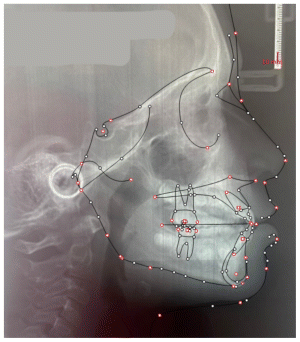

The patient was a growing female child who presented during early mixed dentition with an anterior crossbite associated with a deep overbite and a marked sagittal discrepancy (Figures 12–19). The initial clinical examination revealed a negative overjet, complete anterior deep bite, and a functional Class III occlusal pattern. Extraoral assessment showed a flattened facial profile, while cephalometric analysis confirmed a skeletal imbalance characterized by increased SNA and SNB values, an ANB of 0°, negative Withs appraisal, and significant dentoalveolar compensations, including proclination of both upper and lower incisors (Table 3). The vertical pattern was predominantly hypodivergent, suggesting a high risk of unfavorable mandibular growth progression if left untreated. Given the patient’s young age and growth potential, an early interceptive treatment was planned to use the AMCOP® TC appliance, with the aim of correcting the anterior crossbite, improving neuromuscular balance, and guiding sagittal and vertical development during growth. The appliance was worn nightly and for additional daytime hours, according to patient compliance.

After 18 months of treatment, a clear clinical improvement was observed. Intraoral examination demonstrated complete correction of the anterior crossbite, with establishment of a positive overjet and normalization of the anterior occlusal relationship. The deep bite was reduced, allowing more functional anterior guidance. Occlusal relationships improved toward a stable dental Class I, and the need for excessive dentoalveolar compensation was reduced. Cephalometric reassessment showed an overall improvement in sagittal relationships and incisor inclinations, with a trend toward normalization of the previously altered parameters. These findings indicate that early functional therapy with the AMCOP® TC appliance was effective in intercepting the developing Class III malocclusion, improving occlusal function, and potentially reducing the severity of future skeletal discrepancies (Table 4).

| Parameter | Values | Normal Values |

|---|---|---|

| SNA (°) | 92.2° | 82 ± 3 |

| SNB (°) | 92.2° | 80 ± 3 |

| ANB (°) | 0.0° | 2 ± 2 |

| Overjet (OVJ) | −7.0 mm (Wits) | 3.5 ± 2.5 |

| Overbite (OVB) | ~0 / reduced | 2 ± 2.5 |

| CoGoMe (°) | ~126–128°* | 128.8 ± 4 |

| Upper incisor inclination (Is^Ans–Pns) | ~113.4° | 110 ± 6 |

| Lower incisor inclination (Li^GoGn) | 105.9° | 94 ± 7 |

| Lower incisor compensation (Apg–Li) | ~4.4 mm | 2 ± 2 |

| SNA (°) | 86.9° | 82 ± 3 |

| SNB (°) | 84.3° | 80 ± 3 |

| ANB (°) | 2.6° | 2 ± 2 |

| Overjet (OVJ) | −4.1 mm (Wits) | 3.5 ± 2.5 |

| Overbite (OVB) | Deep bite (reduced) | 2 ± 2.5 |

| CoGoMe (°) | ~128–130°* | 128.8 ± 4 |

| Upper incisor inclination (Is^Ans–Pns) | 111.9° | 110 ± 6 |

| Lower incisor inclination (Li^GoGn) | 101.0° | 94 ± 7 |

| Lower incisor compensation (Apg–Li) | ~3.3 | mm 2 ± 2 |

This case highlights the importance of early diagnosis and timely functional intervention in growing patients, demonstrating how interceptive treatment can favorably influence occlusal development and facial balance during critical growth phases.